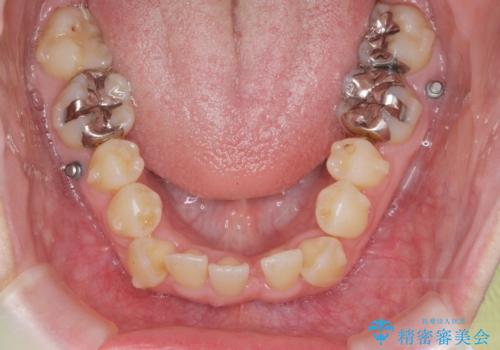

前歯のがたつき すれ違い咬合のマウスピース矯正治療

- 前歯のがたつきや歯の角度、矯正治療を希望され来院されました。

仕事の都合で、ワイヤー矯正を行うことが難しくマウスピース矯正であれば可能、という希望でした。

下顎が前にある咬合関係を可及的に咬合移動で改善し、IPR、下顎3前歯の仕上げで行うマウスピース矯正を計画します。

他院では、「マウスピース矯正では治らない。」と言われ当院に相談に見えましたが、マウスピースで達成できるゴールを模索することで矯正治療を行えることがあります。